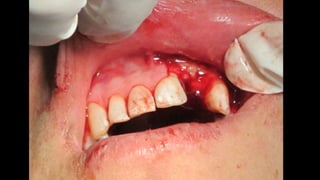

El documento trata sobre la cirugía bucal para plastía del proceso alveolar utilizando hueso humano y factores de crecimiento. También menciona los cuidados postoperatorios, que incluyen el uso de hielo, reposo, dieta líquida y antibióticos, evitando antiinflamatorios no esteroides. Se proporciona información adicional sobre las páginas web relacionadas con cirugía maxilofacial.